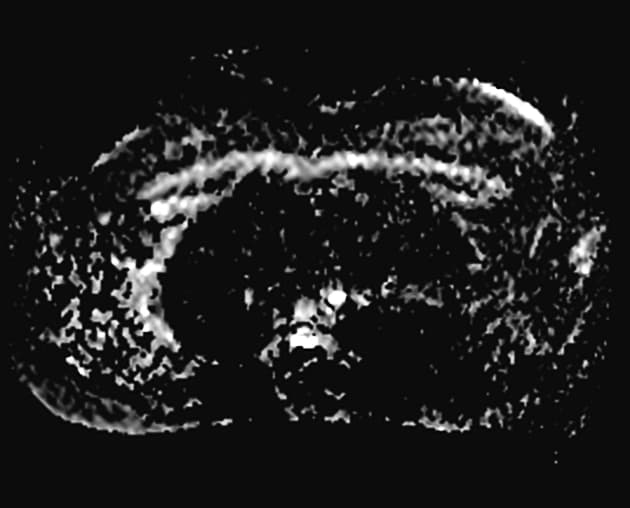

- Tổn thương dạng thùy (lobulated) kích thước 35 x 45 mm nằm ở phân đoạn V của thuỳ phải, liền kề với túi mật (gallbladder).

- Tổn thương này tăng tín hiệu (hyperintense) trên hình ảnh T2-weighted MRI.

- Trên hình ảnh cộng hưởng từ có tiêm thuốc tương phản động (dynamic contrast-enhanced imaging), thấy tăng quang dạng nốt (nodular) ở vùng ngoài viền (peripheral) ban đầu, tiếp theo là quá trình lấp đầy dần từ ngoài vào trong (slow centripetal filling).

- "U sợi mạch gan thường biểu hiện tăng tín hiệu T2 và tăng quang dạng nốt ở viền ngoài với quá trình lấp đầy từ từ từ ngoài vào trong trên cộng hưởng từ có tiêm thuốc tương phản động."

U sợi mạch gan là khối u gan lành tính phổ biến nhất, thường được phát hiện tình cờ trên hình ảnh học. Bệnh xuất phát từ các mạch máu bất thường và gồm các khoang giãn chứa đầy máu được lót bởi tế bào nội mô. Trên cộng hưởng từ (MRI), hình ảnh điển hình bao gồm tăng tín hiệu rõ rệt trên T2 và kiểu tăng quang dạng nốt ở vùng ngoại vi trong thì động mạch, tiếp theo là quá trình lấp đầy dần từ ngoài vào trong ở các thì muộn. Dấu ấn hình ảnh này rất đặc hiệu, cho phép chẩn đoán chắc chắn không xâm lấn trong hầu hết các trường hợp. Mặc dù có thể sinh thiết, nhưng thủ thuật này tiềm ẩn nguy cơ chảy máu và thường được tránh. Điều trị mang tính bảo tồn, không cần cắt bỏ hay theo dõi định kỳ trong các trường hợp điển hình, trừ khi có nghi ngờ chẩn đoán hoặc bệnh nhân có triệu chứng.